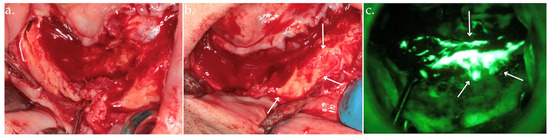

2.2. Autofluorescence-Guided Surgery